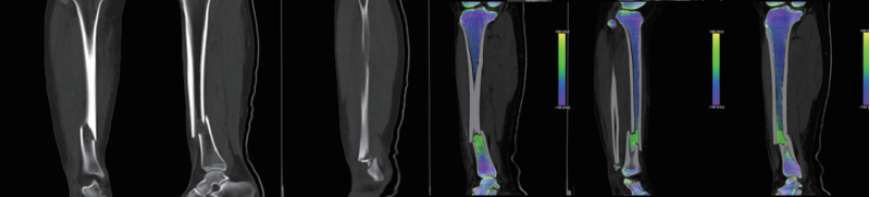

案例圖

骨髓顯像